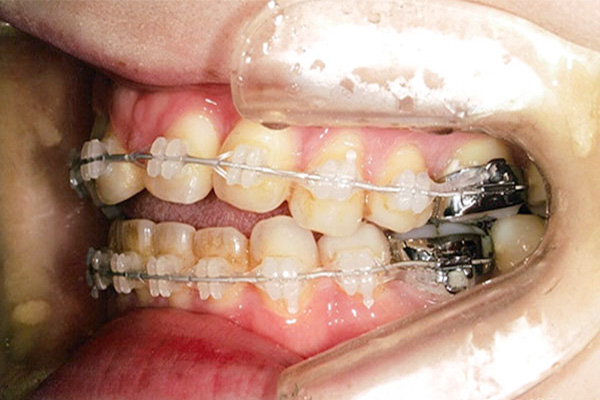

2年1ヶ月後